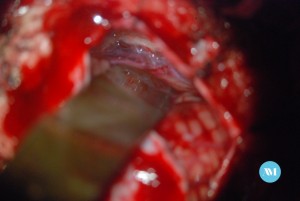

Algunos pacientes pueden requerir cirugía para aliviar la presión sobre el nervio. Las técnicas:

- Cirugía para extirpar un vaso sanguíneo que está ejerciendo presión sobre el nervio trigémino (llamada descompresión microvascular o DMV).